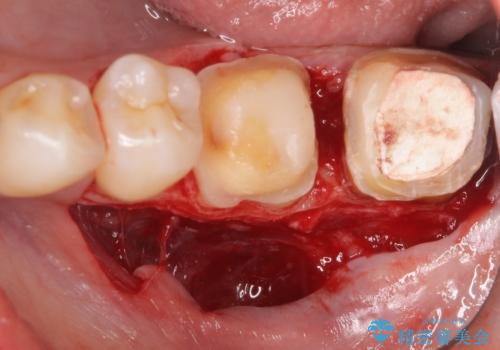

- 左下奥歯で咬むと違和感があるといらっしゃった方の症例です。

検査の結果左下7は失活(歯の神経が死んでいること)しておりX線上で根尖病変を認めたため、根管治療を行いました。

また左下6は遠心にあった歯茎より深い虫歯(縁下カリエス)の問題を解決するため、歯茎を下げる歯周外科手術を行いました。